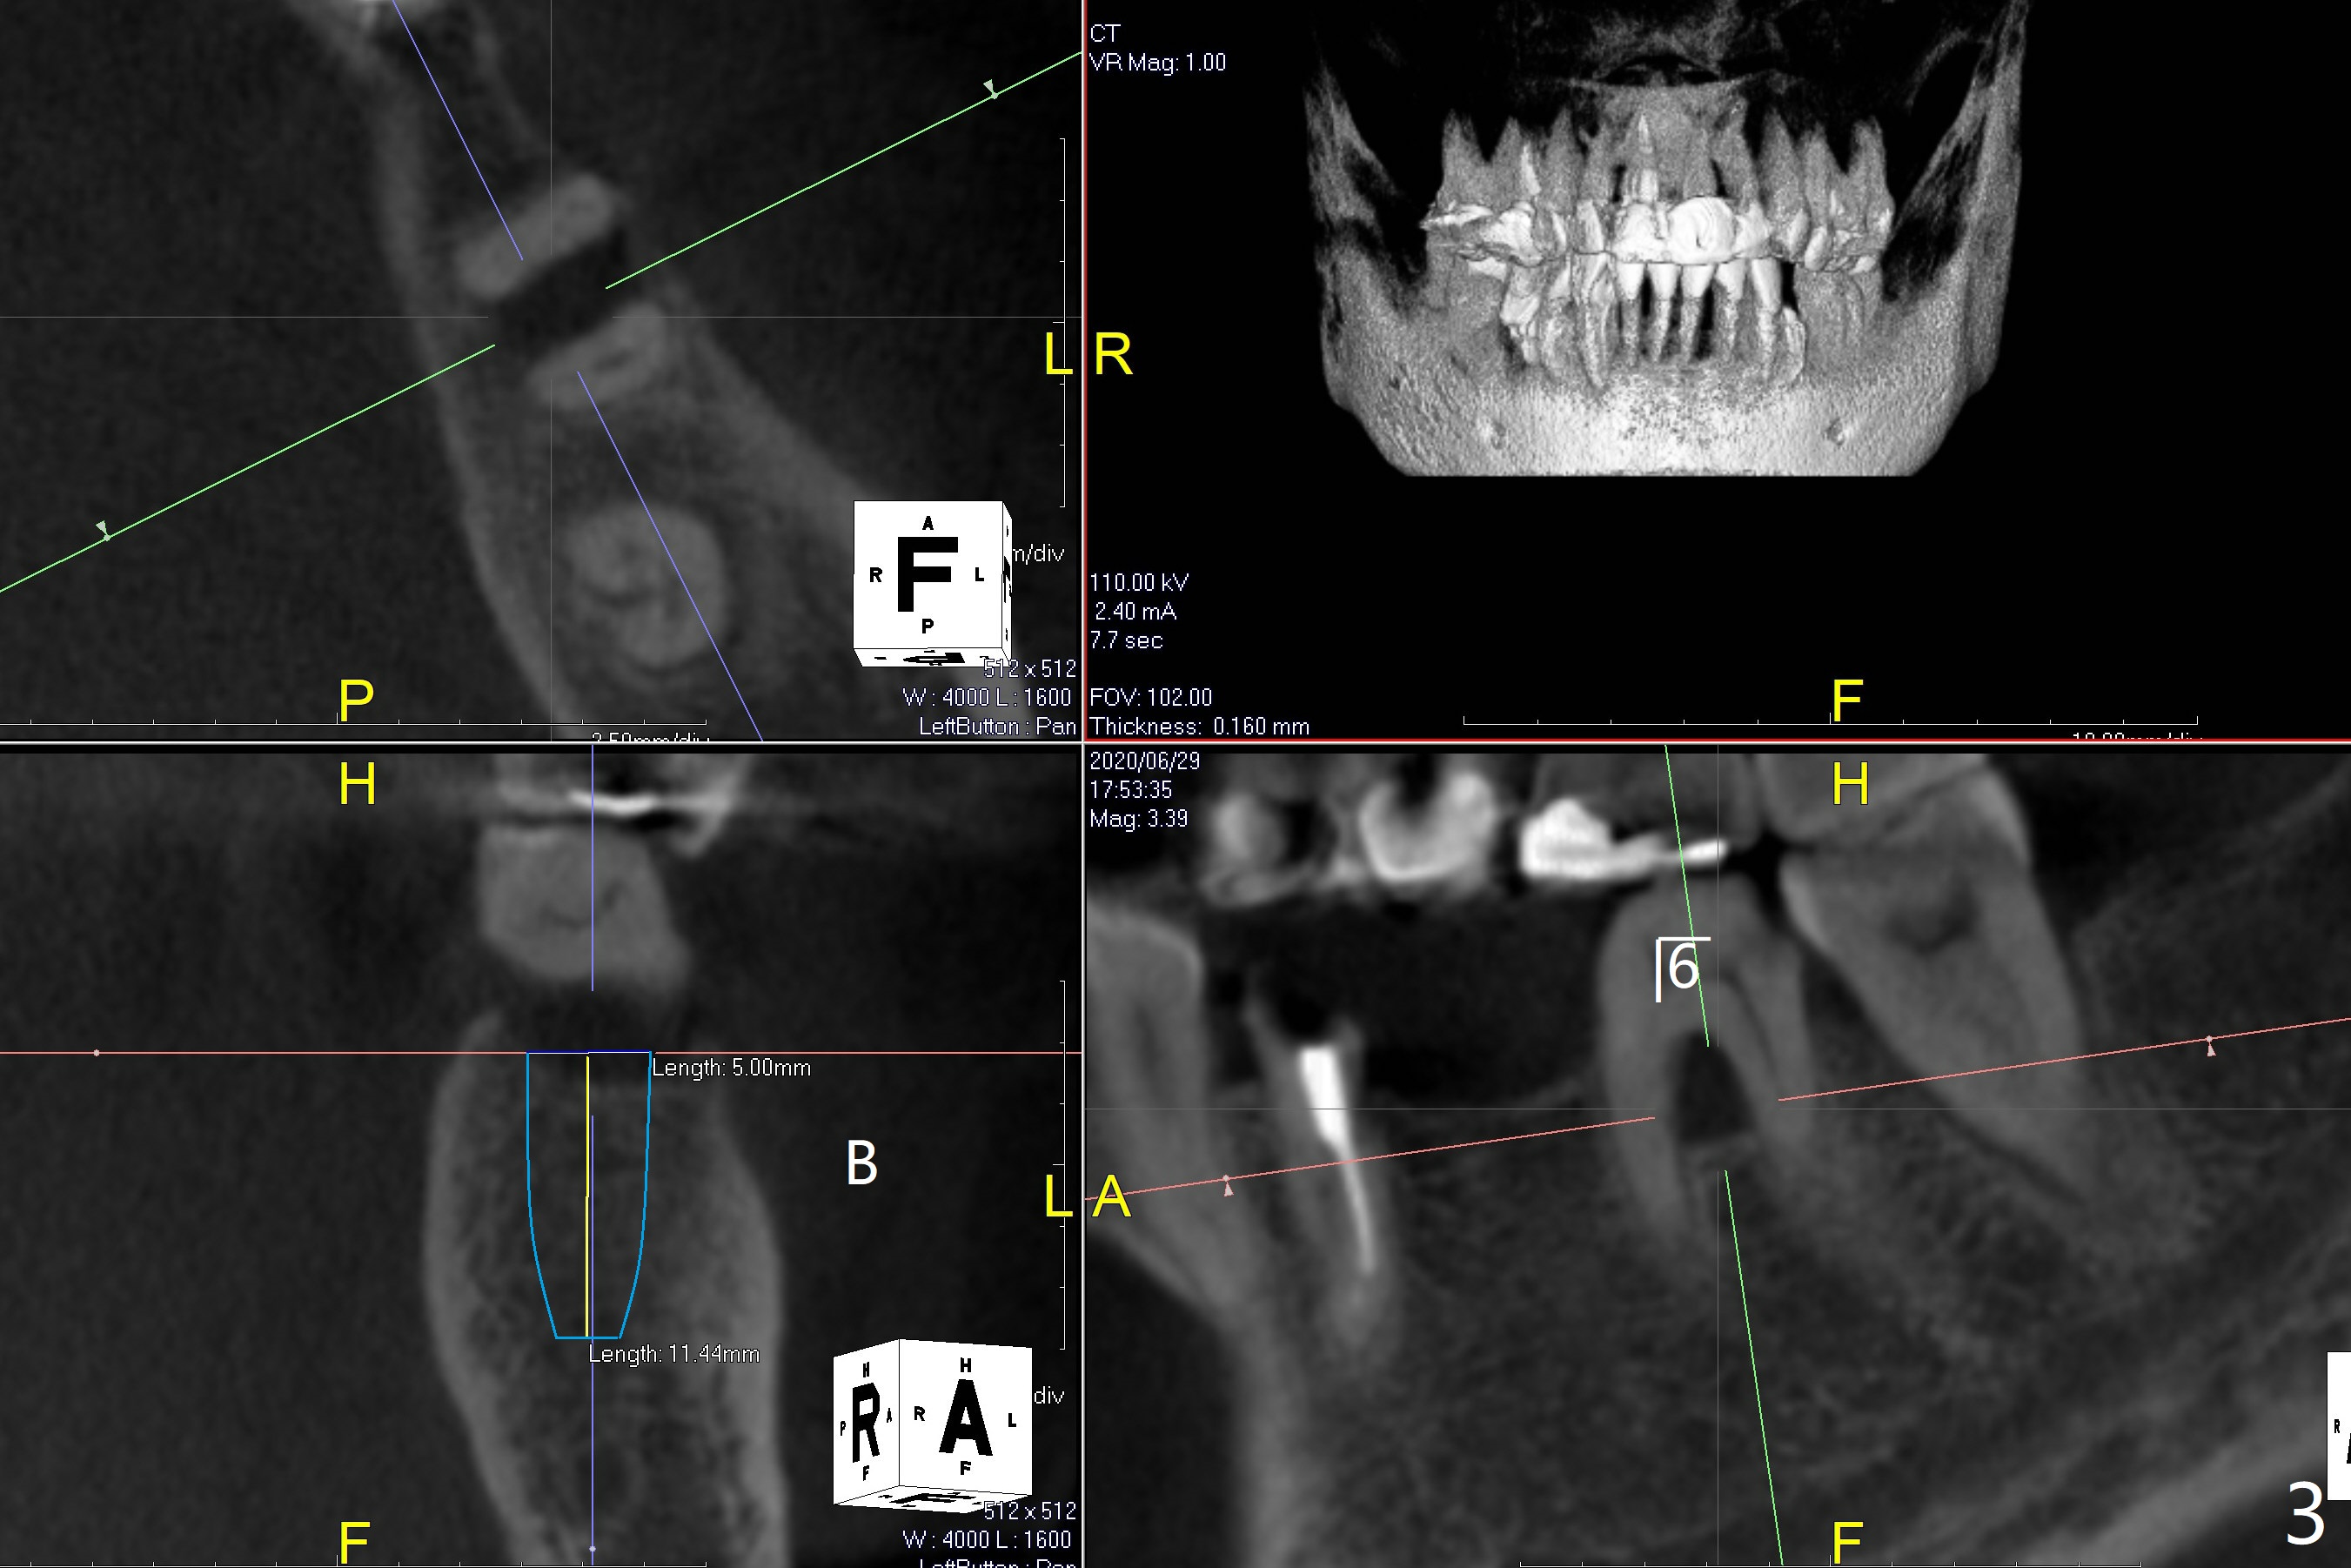

63岁女对肾上腺素和90%以上抗生素过敏,左上5(短根,巨大根尖阴影,图一),左下6(根分叉感染,远中龋齿(图二:*),左下4(牙齿断裂略微龈下:图二,五)似乎很难保留,左下5骨质宽度,高度也允许植牙(图四)。由于左上5需要提升术,可能出现上颌窦感染,Z Pack是否引起过敏反应不确定,拔牙植骨与提升植牙分期做(术前拍摄根尖片)。而下颌一期完成。